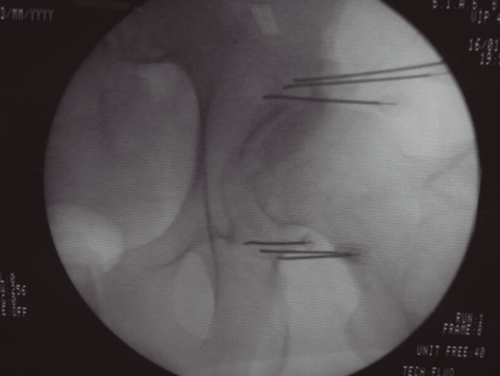

Figura 1